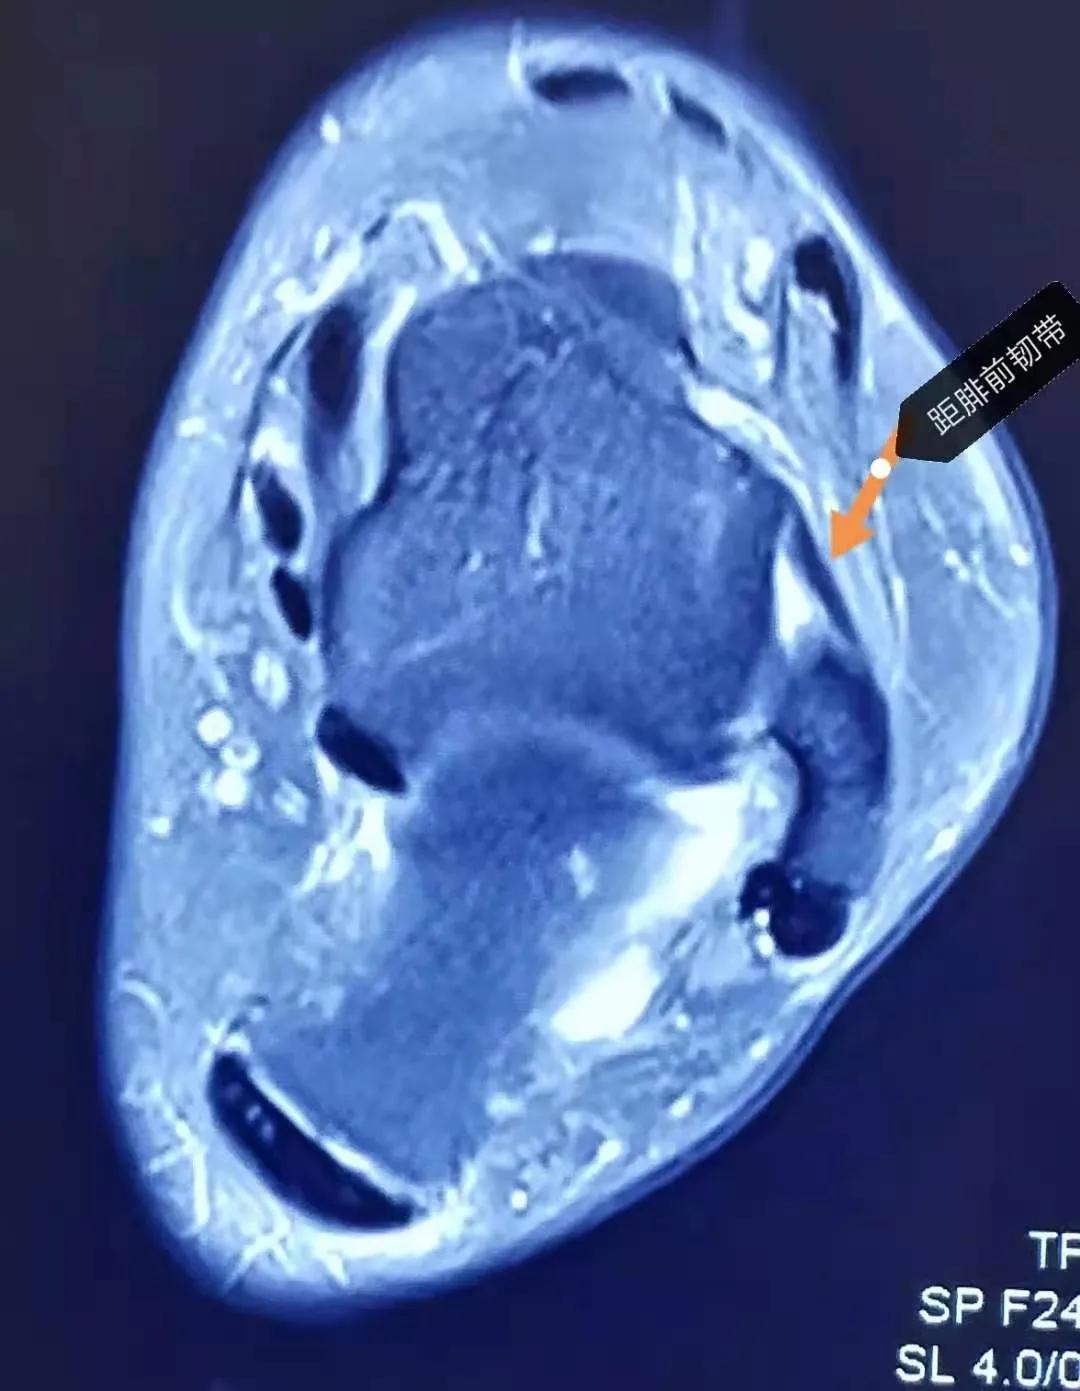

而下图(蓝*图色**)是一张完全正常的踝关节核磁影像,箭头指示是完全正常的距腓前韧带,在核磁上表现为黑色(低信号)的条状结构。所以通过两幅图的对比,我们可以确诊患者是距腓前韧带的损伤(跟腱受伤后这些要做的检查一定得知道 )。